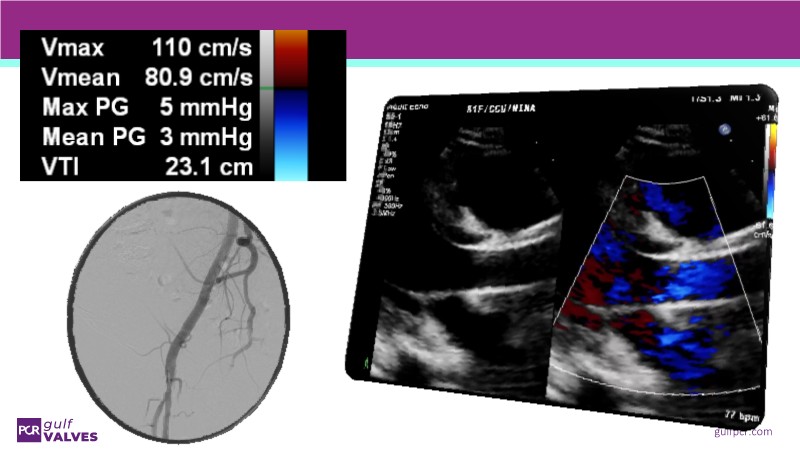

Join this comprehensive session to explore the Myval transcatheter heart valve series, featuring the latest clinical updates from two large randomized controlled trials—Landmark and Compare TAVI. Learn from real-world experiences, including recorded cases, and understand how these innovations translate to complex patient demographics in daily TAVI practice.